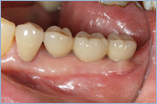

現在はインプラント治療は一般的に行われています。

治療中はムシ歯の治療など使用している局所的な麻酔で行えます。ほとんどの場合可能ですが専門医がくわしく診断し最善の方法をおすすめします。

※インプラントをより長くお使いいただくために定期的にクリーニングに来ていただき状態をチェックさせていただきます。

インプラント

¥280,000(被せ物は除きます)

※消費税は別にかかります。